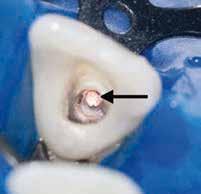

1. a–f ábrák: A cingulumon keresztül gömbfúróval kialakított hozzáférés a trepanációs kavitás labiális irányba történő túlzott mértékű kiterjesztését eredményezheti, és ez lényegesen növelheti a perforáció esélyét (a). A guttapercha átsejlik a lágyrészek alatt (b). Klinikailag igazolt perforáció (c). A preoperatív sagittális irányú CBCT-szeleten jól látható a labiális perforáció (d). Labiális irányú perforáció (fekete nyíl; e). A tényleges gyökércsatorna (piros nyíl; f).

2. a-b ábrák: A cingulumon keresztül gömbfúróval végzett trepanálás túlzott pericervikális dentin áldozattal, fordított tölcsér effektussal és perforációk kialakulásával járhat (fehér nyíl).